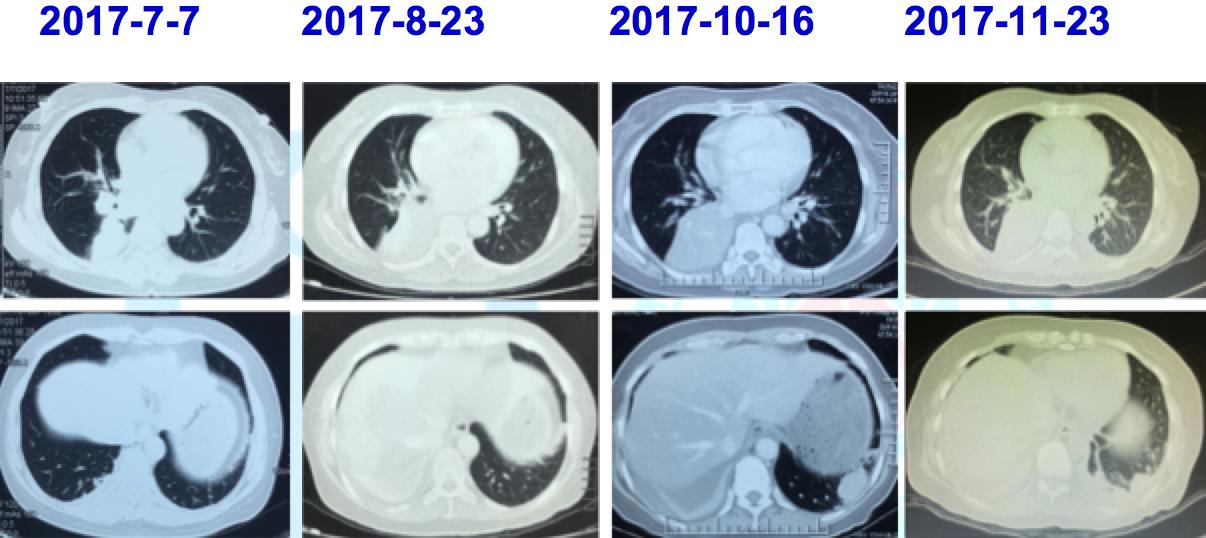

1. 一线:2017-7-22开始口服易瑞沙,2017-8-23CT示右肺病灶增大,大脑右侧额叶转移,PD,PFS=1月

2. 二线:入组中山大学肿瘤医院TQ-B3139胶囊(ALK*制剂抑**,克唑替尼类似物,正大天晴)I期临床研究,于2017-9-18开始TQ-B3139 50mg Qd, 2017-10-16CT示腹腔淋巴结多发转移,多发骨转移,PD,PFS=1月

3. 三线: 2017-10-18予以培美曲塞800mg+卡铂500mg化疗,出现气促,3度骨髓抑制,4度肝功能损害。2017-10-23血液NGS:ROS1基因融合,METexon16错义突变。2017-11-22MRI脑转移病灶增多,脑膜转移。2017-11-23CT左下肺病灶缩小36%。出现左足第三趾皮色发黑,PS=2分。